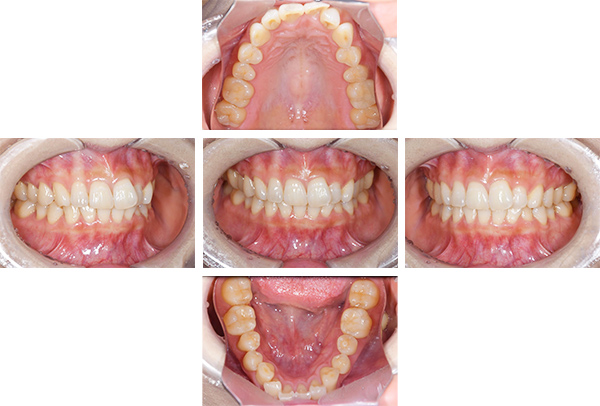

症例写真(治療後)

担当医師所見

治療後:

矯正治療と虫歯の治療すべて終わったときの写真になります。見た目も最初の頃とは全く違いますし、お口の中もすごく綺麗です。

治療

方針

まずは虫歯の治療を行い、被せ物をする部分は仮歯をいれて矯正を行う。矯正終了後、仮歯の部分を最終的な被せ物に変えていく。また気になっていた銀歯もセラミックに変えて終了となった。